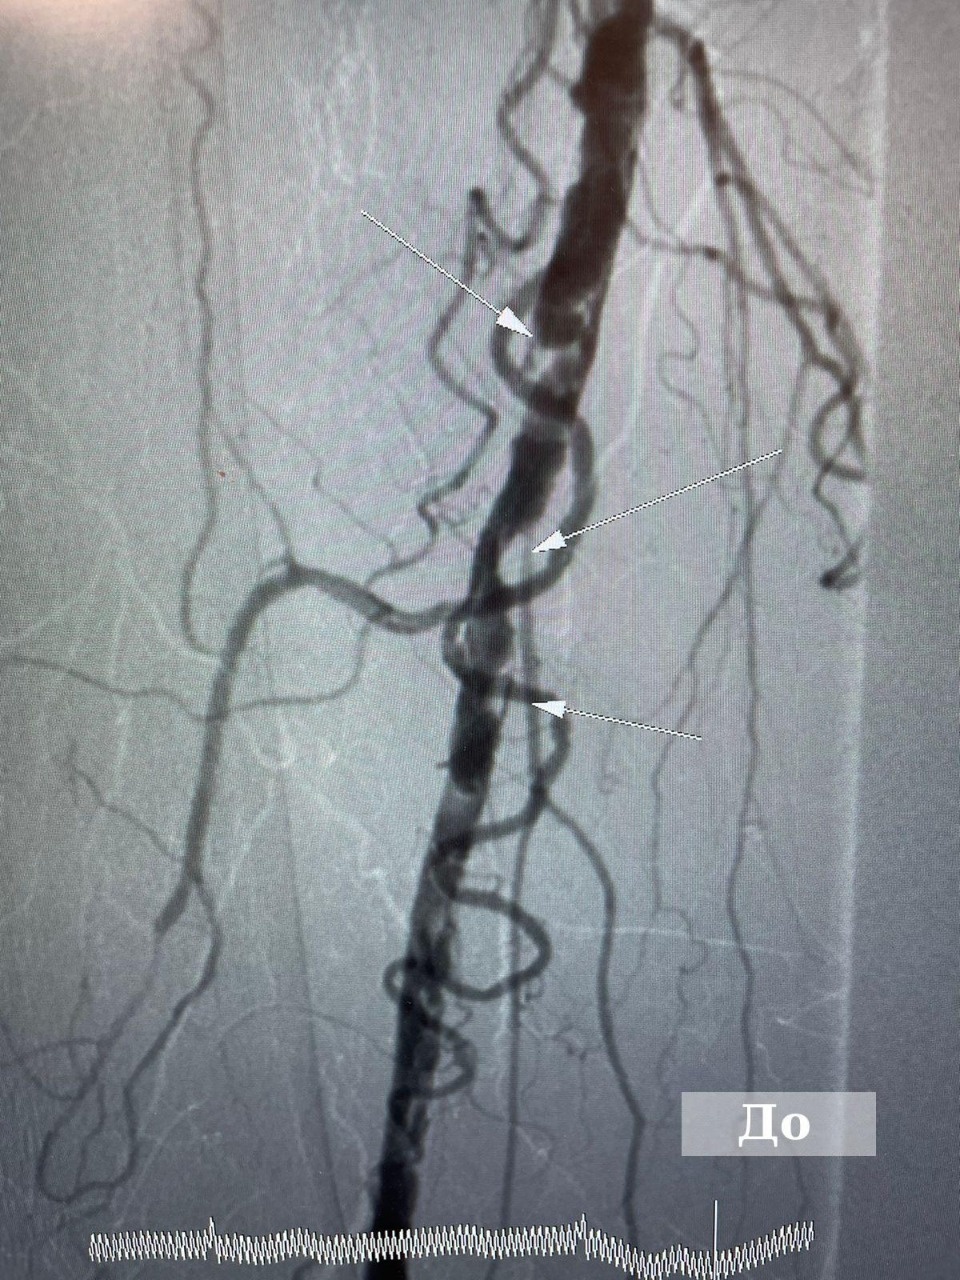

90-летней пациентке провели высокотехнологичную операцию на артериях в Великих Луках

Фото: комитет по здравоохранению Псковской области

Операцию сделали в отделении рентгено-хирургических методов диагностики и лечения Великолукской межрайонной больницы. У пожилой пациентки развивалась гангрена на правой ноге.

Заведующий РХМДиЛ Алексей Горин поделился, что для сохранения конечности специалисты решили провести пенсионерке малоинвазивную операцию с имплантацией стента, в результате у пациентки восстановилась проходимость артерии.